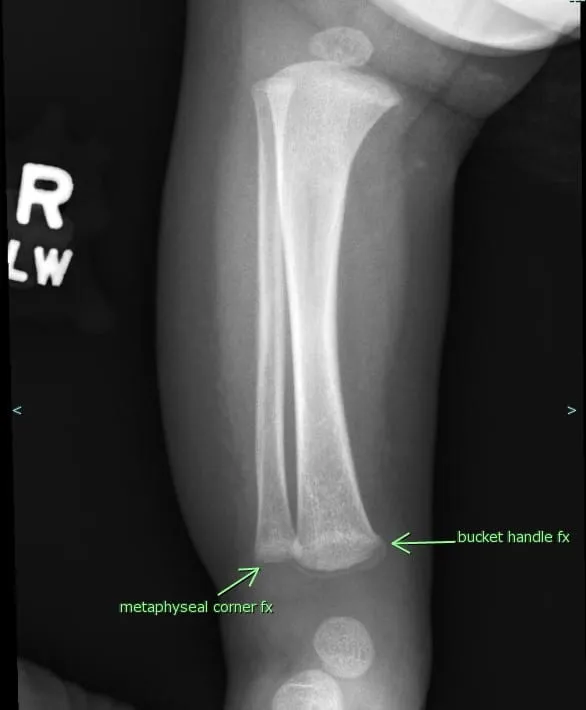

- Non-Accidental Injury (NAI):

- Red Flags: Story-injury mismatch, multiple fractures (varied healing), bruises in pre-ambulatory infants.

- Highly specific: Metaphyseal corner fx, posterior ribs, sternal fx.

- Action: High suspicion, document meticulously, report (CWC/POCSO Act), ensure child safety.

⭐ Metaphyseal "corner" or "bucket-handle" fractures are virtually pathognomonic for NAI.

- Suspect non-accidental injury (NAI) with metaphyseal corner fractures, posterior rib fractures, or multiple fractures in varied healing stages.